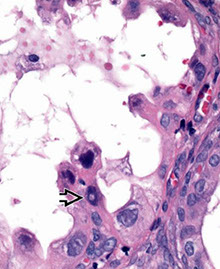

Arias-Stella Reaction

Found in up to 2/5 pregnancies, or in pts on OCPs or idiopathic

- affects superficial or deep glands and can be local or diffuse

- usually a focal finding, when seen in curetting is assoc c intrauterine and ectopic gestations

Micro: big cells that can look red or c big vacuoles or hobnailed, irreg nuclei sometimes hyperchromatic

- can form papillary tufts or cribriform

- low mits, rare pseudoinclusions in nucleus, occasional decidualization of stroma

- can mimic AIS or clear cell ca

Arias Stella Reaction